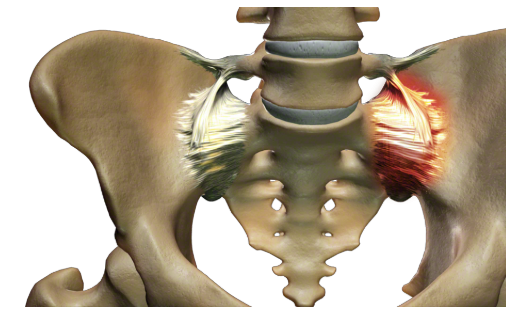

The SI joint can be a significant cause of lower back pain. Clinical publications have identified the SI joint as a pain generator in 15-30% of chronic lower back pain patients.1-4 In addition, the SI joint is a pain generator in up to 43% of patients with continued or new onset lower back pain after a lumbar fusion.

Like any other joint in the body, the SI joint can be injured and/or undergo degeneration. When this happens, people can feel pain in their buttock and sometimes in the lower back, hips and legs. This is especially true while lifting, running, walking or even lying on the involved side.

It’s common for pain from the SI joint to feel like disc or lower back pain, or sometimes hip or groin pain. For this reason, SI joint disorders should always be considered in lower back, hip, and pelvic pain diagnosis.

Do you experience one or more of the symptoms listed below?

- Lower back pain

- Sensation of low extremity: pain, numbness, tingling, weakness

- Pelvis/buttock pain

- Hip/groin pain

- Feeling of leg instability (buckling, giving way)

- Disturbed sleep patterns due to pain

- Disturbed sitting patterns (unable to sit for long periods, sitting on one side)

- Pain going from sitting to standing

| SI joint pain can mimic pain in the lower back, hip, groin, or pelvis. | Patients who suffer from SI joint dysfunction can have severe pain when performing transitional movements like standing from a chair. | Patients who have SI joint pain usually find it difficult to sit for long periods of time, and usually try to alleviate the discomfort by sitting on the least effected side. |